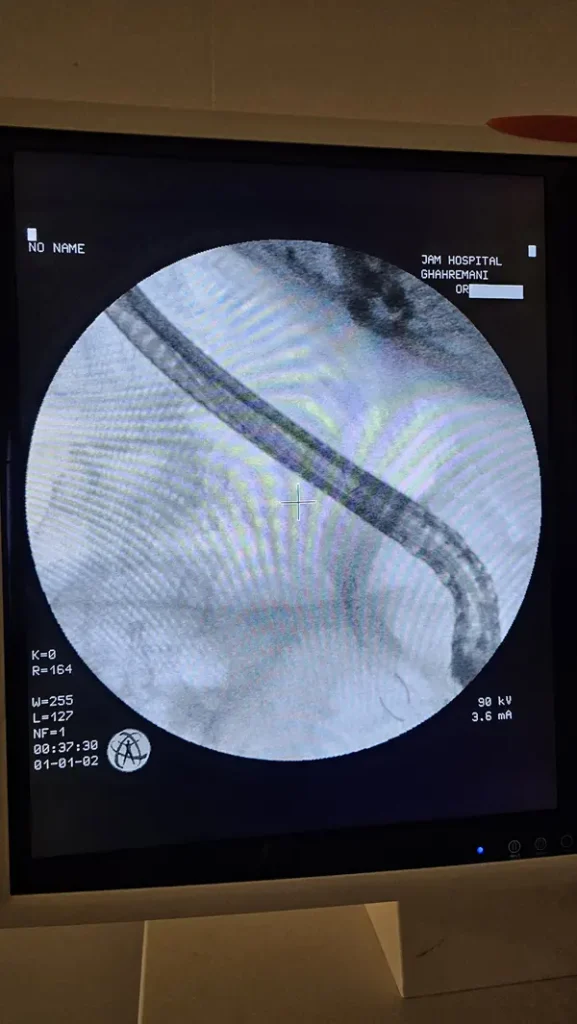

درباره ERCP بیشتر بدانیم

ERCP یک نوع تصویر برداری است که همانند آندوسکوپی از طریق دهان لوله ای وارد می شود. و از مجموعه صفراوی و پانکراست تصویربرداری انجام می شود.

در ادامه تصاویر و فیلم ERCP آقای ۶۶ ساله دارای سرطان سر پانکراس که غیر قابل عمل بود را مشاهده مینمایید.

ای آر سی پی در تشخیص سنگ های صفراوی، زخم ها، سرطان ها، تومورها و ضایعات احتمالی در لوزالعمده و پانکراست کاربرد دارد.

با استفاده از ERCP زردی و یرقان که در اثر انسداد مجاری صفراوی به وجود می آید را می توان درمان نمود.

همچنین بالن های خروجی سنگ های صفراوی با استفاده از ای ار سی پی انجام می شود.

مزیت ای آر سی پی در جلوگیری از جراحی های باز است.

نمونه هایی از عمل جراحی ERCP توسط دکتر رضادوست